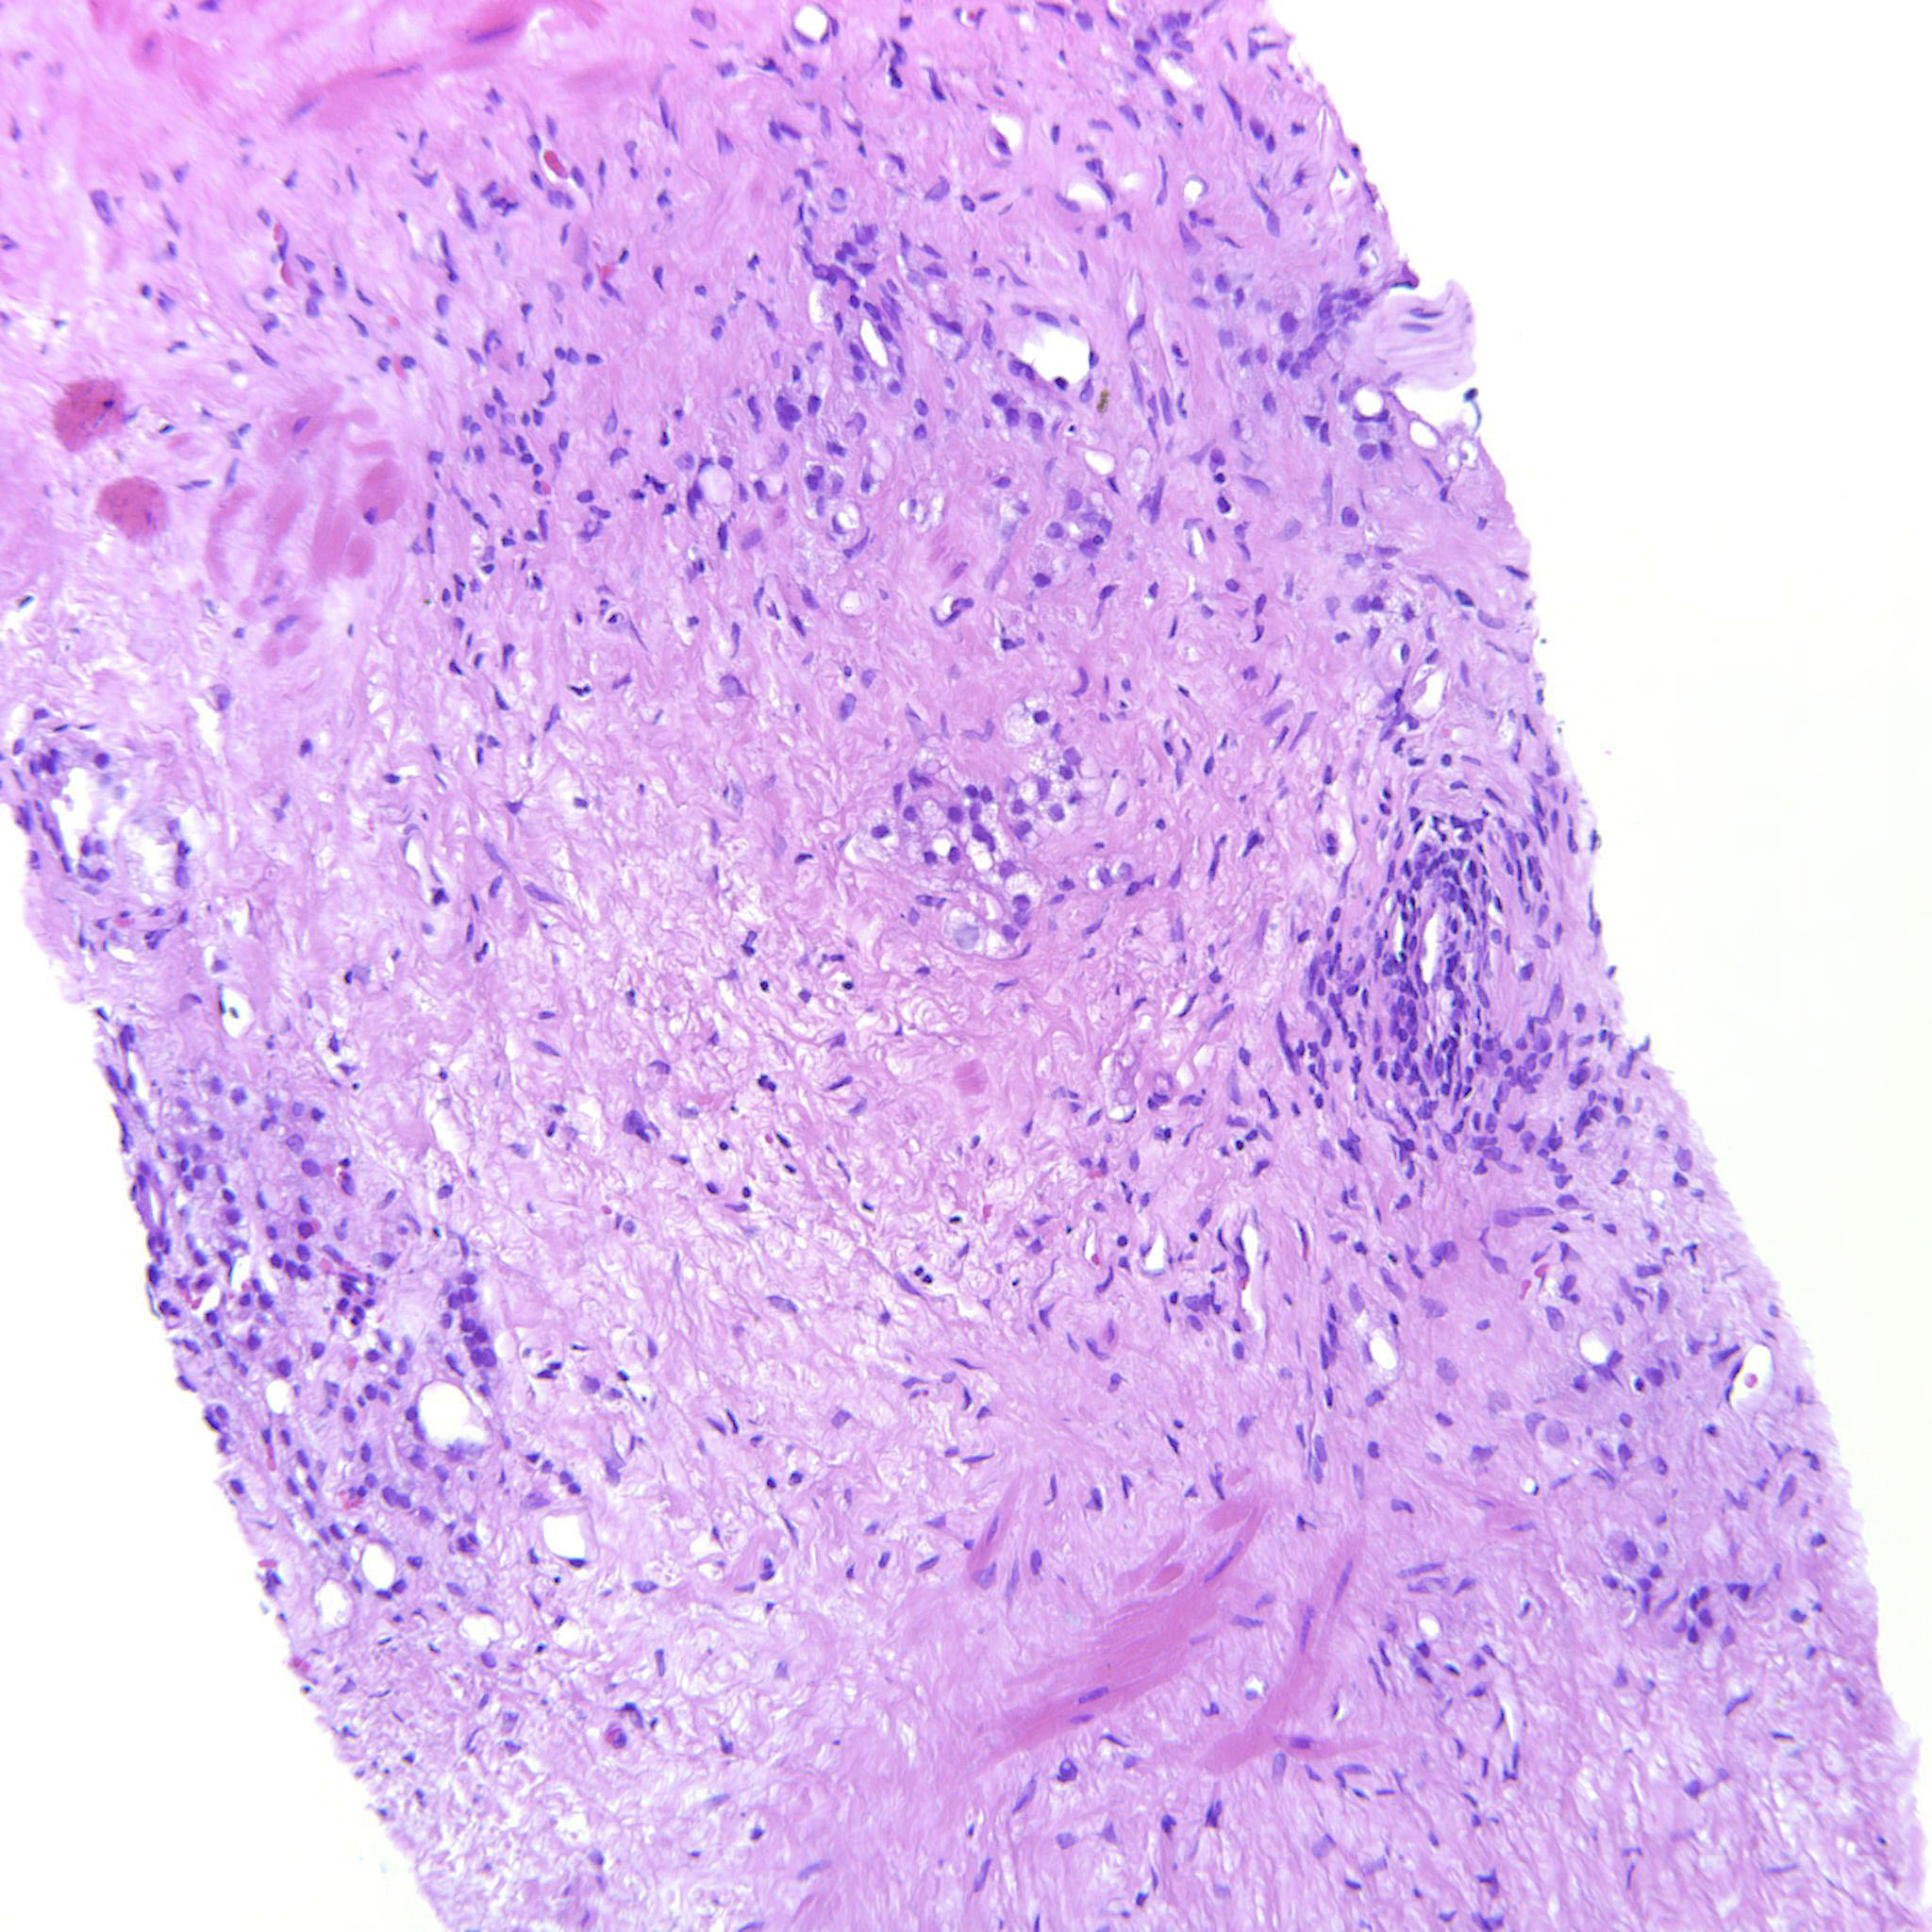

Prostate cancer grading

Case ID: 635